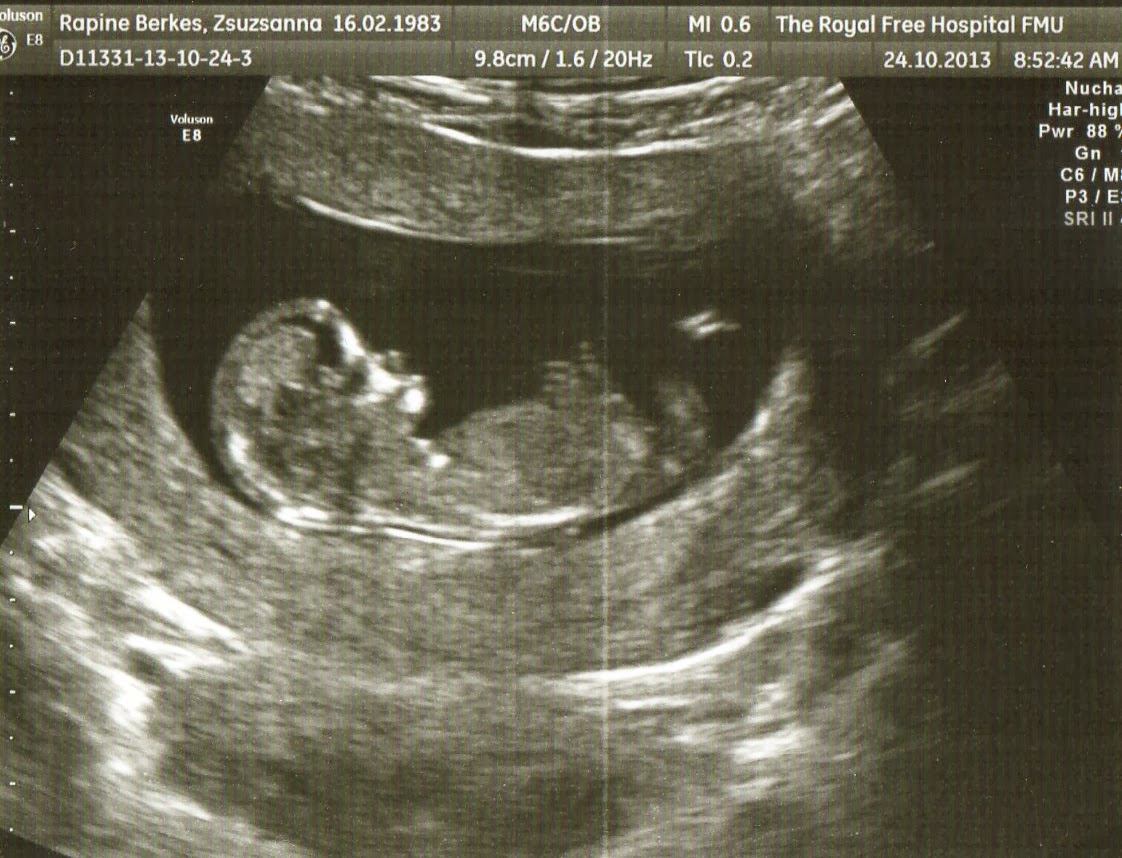

Elmentem a haziorvoshoz, itt csak GP-nek hivjak. O konkretan felvette az adatokat majd annyit mondott hogy postan varjam az ertesitot az Ultrahang vizsgalatrol. En naiv azt hittem legkesobb kovetkezo heten megkapom De utanajarasomat kovetoen radobbentem hogy Angliaban osszesen ket UH (ultrahang) van 12. es 20. heten (hacsak nincs vmi komoly panasz) Eloszor okt. 15.-re kpatunk idopontot a Royal Free Korhazba. Elsore nagyon szep modern korhaznak tunt. Illetve egybol a dawn szindorma szures miatt vert is vettek tolem. A ultrahangon viszont kiderult, hogy a baba a meretei alapjan meg nincs 11 hetes se, ezert tul korai igy azon kivul hogy fel pillanata belehallgattunk a szivhangjaba, meg megmutatta, hogy megva mindket keze laba, mast nem is vizsgalt, csak annyit mondott hogy vissza kell jonni 2 heten belul, a 12 hetes ultrahangra. Igy kertunk egy ujabb idopontot okt. 24-re. Ekkor mar 11 het es 6 naposak voltunk. Szerencsere minden rendben volt. CRL (ulomagassag): 54.3 mm, NT (nyakiredo): 0.9 mm

Legkozelebb dec. 15.-en megyunk UH-ra.